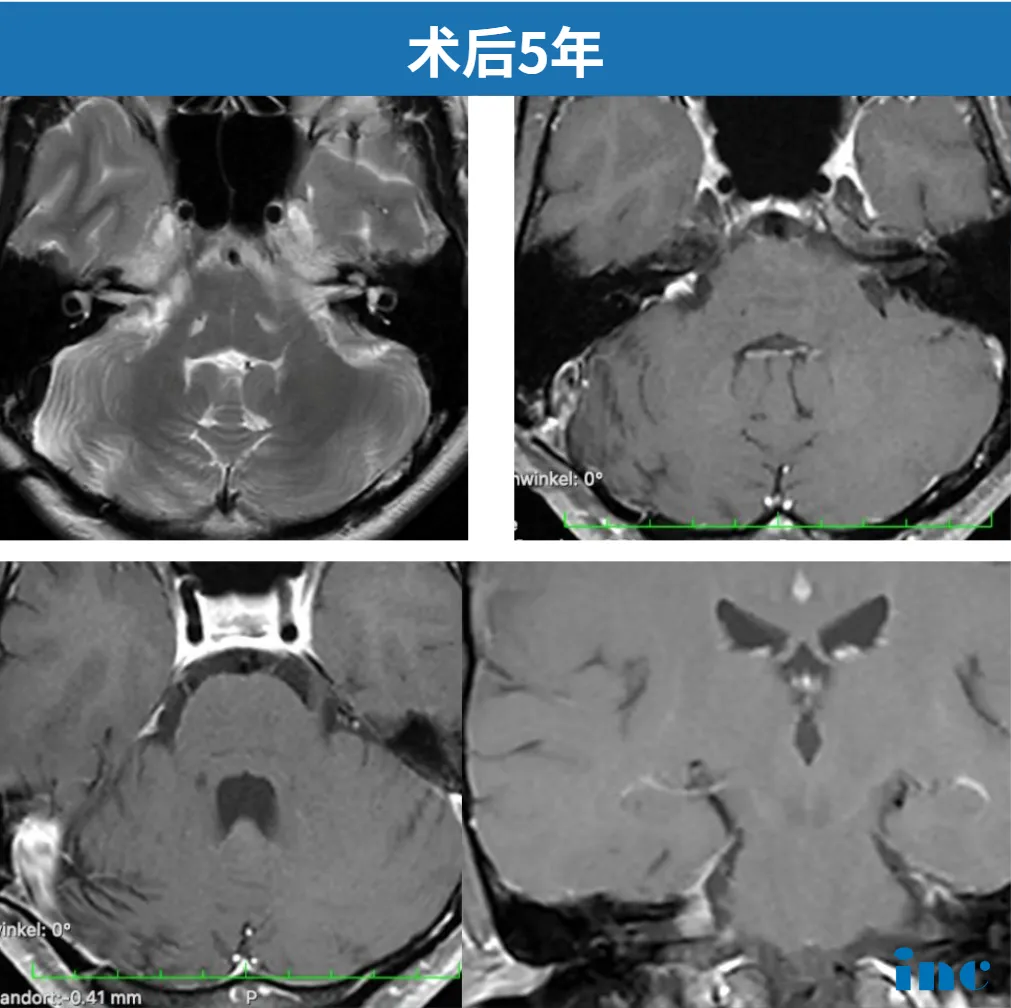

2025年11月3日,术后第五年的磁共振复查结果显示:"影像学表现非常理想",未见肿瘤残留或复发征象。目前阿岚已完全康复,恢复正常工作和生活。